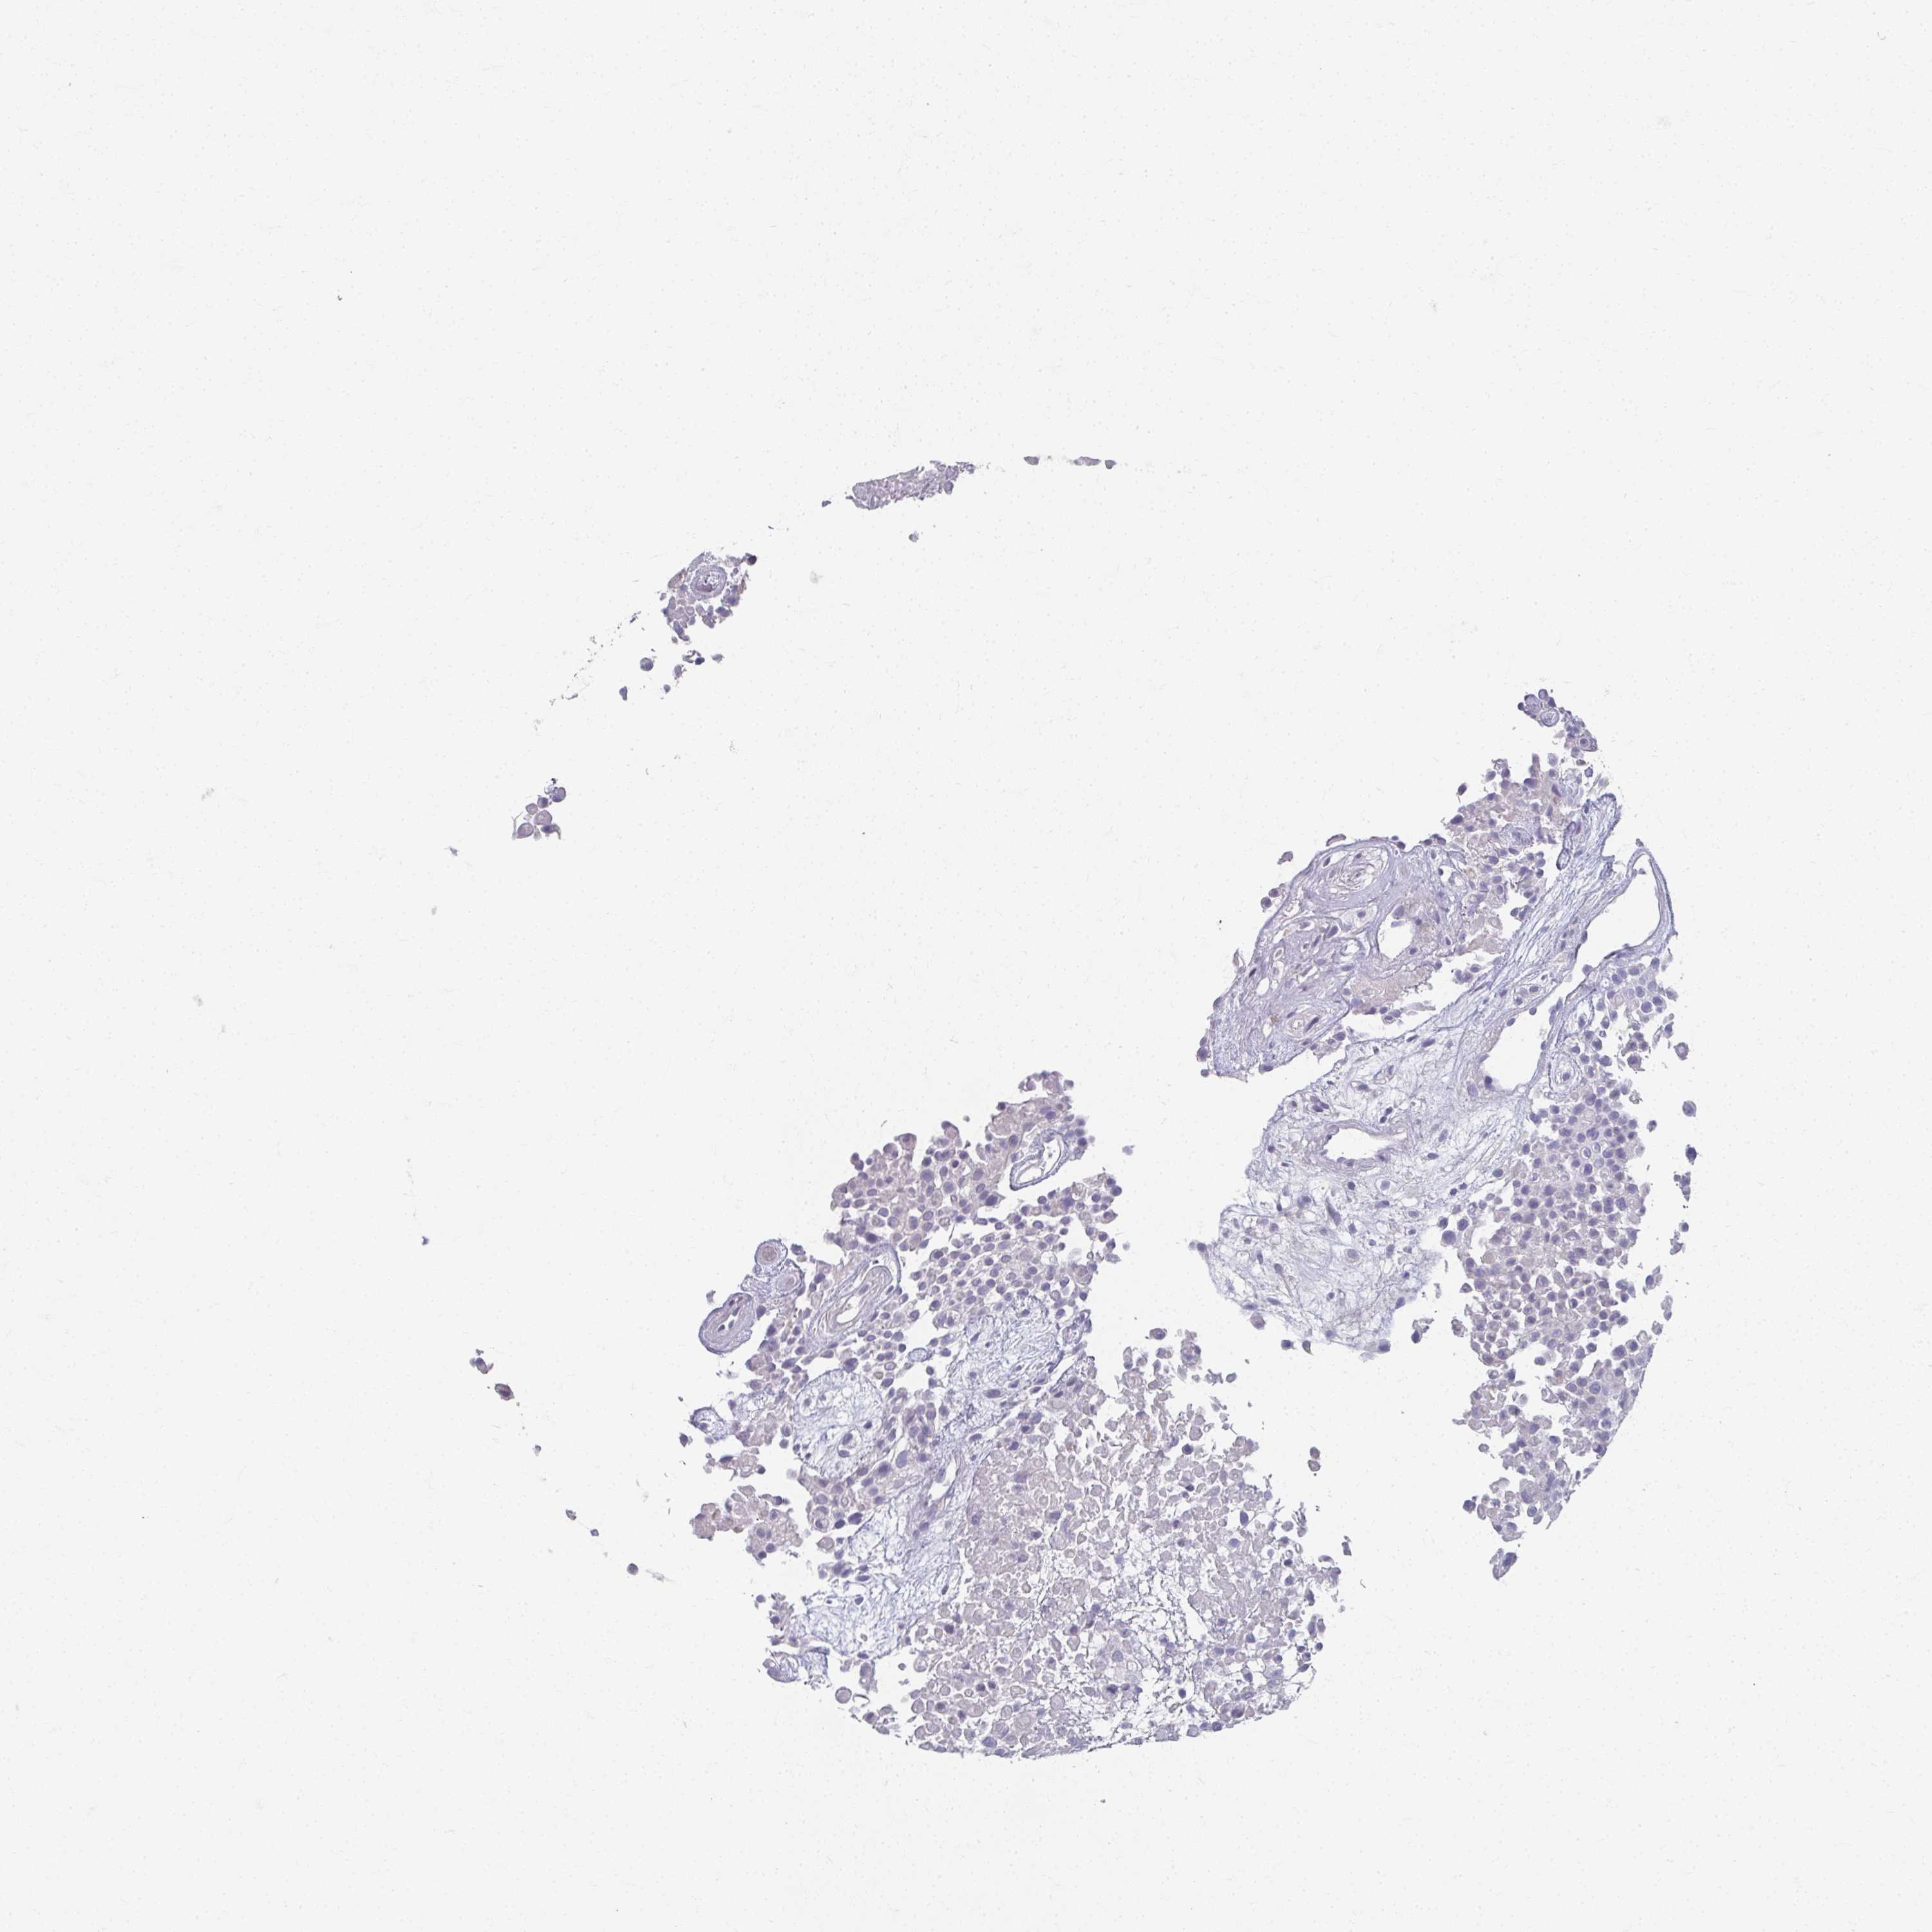

UROTHELIAL CANCER - Protein expressioni

A mouse-over function shows sample information and annotation data. Click on an image to view it in a full screen mode. Samples can be filtered based on level of antibody staining by selecting one or several of the following categories: high, medium, low and not detected. The assay and annotation is described here.

Note that samples used for immunohistochemistry by the Human Protein Atlas do not correspond to samples in the TCGA dataset.

Antibody stainingi

Antibody staining in the annotated cell types in the current human tissue is reported as not detected, low, medium, or high, based on conventional immunohistochemistry profiling in selected tissues. This score is based on the combination of the staining intensity and fraction of stained cells.

Each image is clickable and will lead to virtual microscopy that enables deeper exploration of all samples and also displays staining intensity scores, fraction scores and subcellular localization as well as patient and tissue information for each sample.

Antibody HPA007656

Antibody CAB034931

Urothelial carcinoma, High grade

Urothelial carcinoma, NOS

Urothelial carcinoma, Low grade